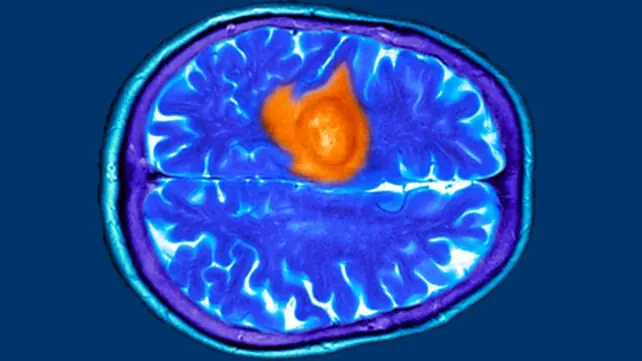

Brain cancer comes in two varieties: Primary tumors, which start in the brain and rarely spread, and secondary tumors, which start elsewhere in the body (typically the lungs or breasts) and spread to the brain, says Adilia Hormigo, M.D., Ph.D., director of neuro-oncology at the Mount Sinai Health System and associate professor of neurology, medicine and neurosurgery at the Icahn School of Medicine at Mount Sinai.

Over time, brain cancer can impact surrounding brain cells to seriously compromise brain function. And while that's true of all brain tumors, malignant or benign, cancerous tumors are more likely to spread throughout the brain, and quickly, according to Hormigo. That's why malignant tumors require aggressive treatments, typically including surgery, radiation, and/or chemotherapy, she says.

“With brain tumors, the symptoms sometimes depend on the area of the brain where the tumor is located,” says Hormigo. So if a tumor happens to be behind your eye, that could compromise your vision.

“One of the classic situations I see is a driver causing a car accident because something is messing with their visual field,” she says. So pay close attention to your eyesight and get your eyes checked out regularly. (Preferably every year.) A brain tumor could cause blurry vision, double vision, and loss of vision, and even cause floating shapes or spots to appear, she says.